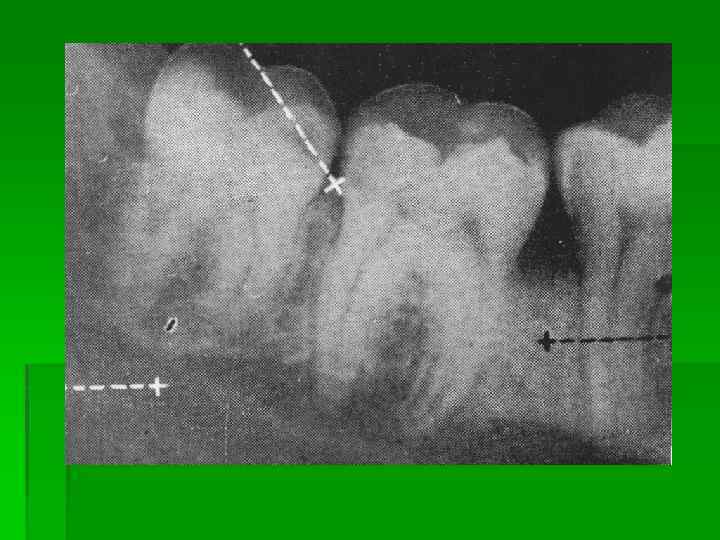

Сиалография